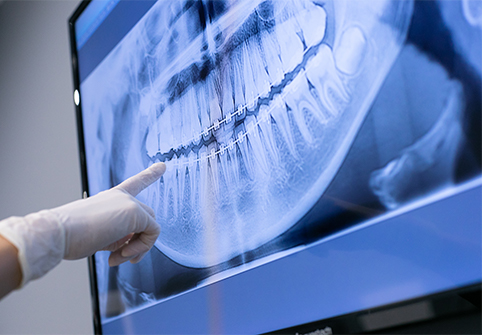

• Radiografías (ortopantomografía y teleradiografía)